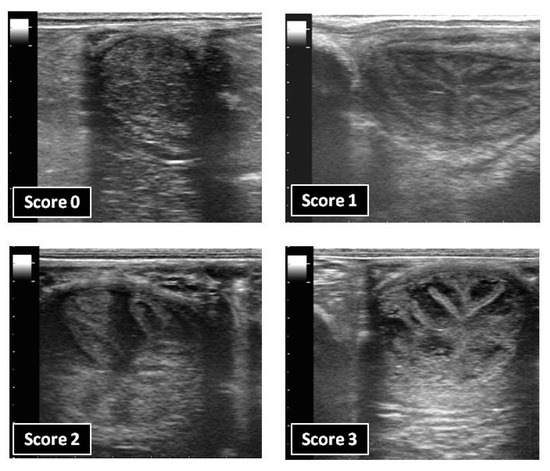

After each treatment, the uterus of the mares was examined daily by transrectal ultrasonography with a scanner Mindray DP-6600 vet (Mindray Brasil, Sao Paulo, Brazil), equipped with a linear array transducer of 7 MHz, to determine the endometrial oedema score for a total of 7 days or until the endometrial oedema had returned to basal. The presence of the endometrial oedema was scored subjectively by the same operator on a scale of 0 (minimum degree of endometrial folding) to 3 (maximum degree of endometrial folding) (Figure 1), as described previously [9].

Figure 1. Representative B-mode ultrasonograms of the endometrial oedema scoring system.